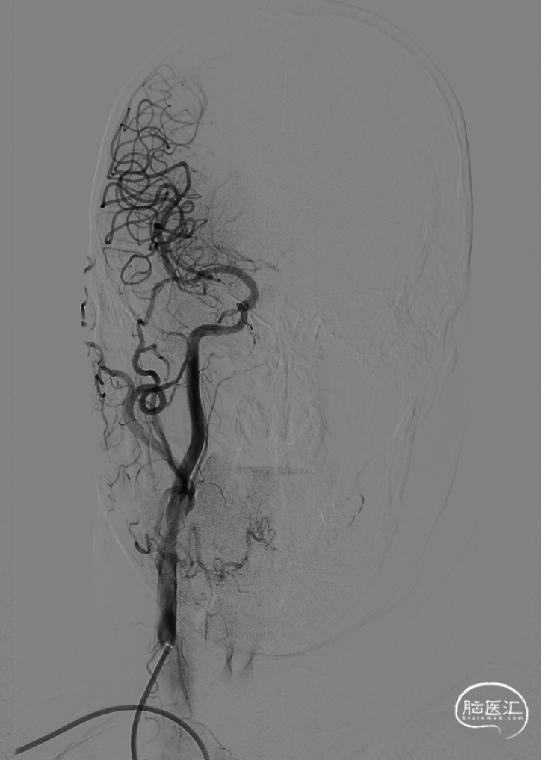

小心缓慢释放支架,支架完全释放后手推造影,见支架位置良好,打开较好,原狭窄明显改善,残余狭窄20%。

术后正位造影: